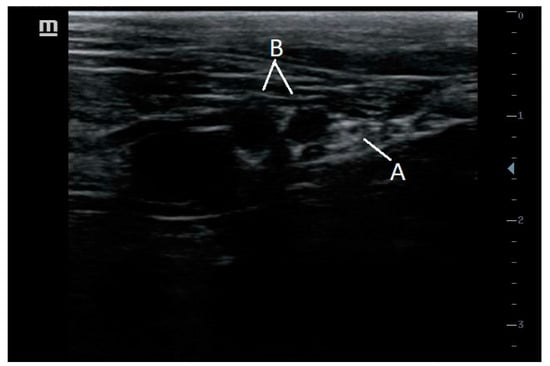

8.1. Femoral Nerve